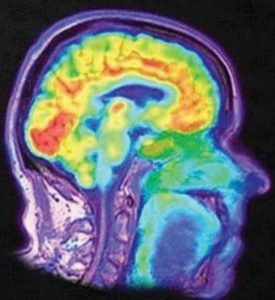

Medical imaging seeks to reveal the internal structures hidden by the skin and bones in order to diagnose and treat diseases. It comprises different types of modalities depending on the physical nature of the waves used and the method of image capture, such as X-ray, MRI, CT, ultrasound, etc. Medical imaging can be used for both diagnostic and therapeutic purposes and is an essential component of clinical practice and the healthcare system.

VIRTUAL AND AUGMENTED REALITY (VR/AR) AND 3D MEDICAL IMAGING: VR/AR and 3D technologies are becoming increasingly popular in the field of medical imaging due to their ability to provide a more immersive and interactive experience. VR/AR and 3D technologies allow medical professionals to visualize medical scans in a 3D environment, which allows better interpretation and diagnosis of medical conditions. These technologies can create detailed models of a patient's anatomy, helping medical professionals better understand complex medical conditions and plan ahead of a medical procedure.